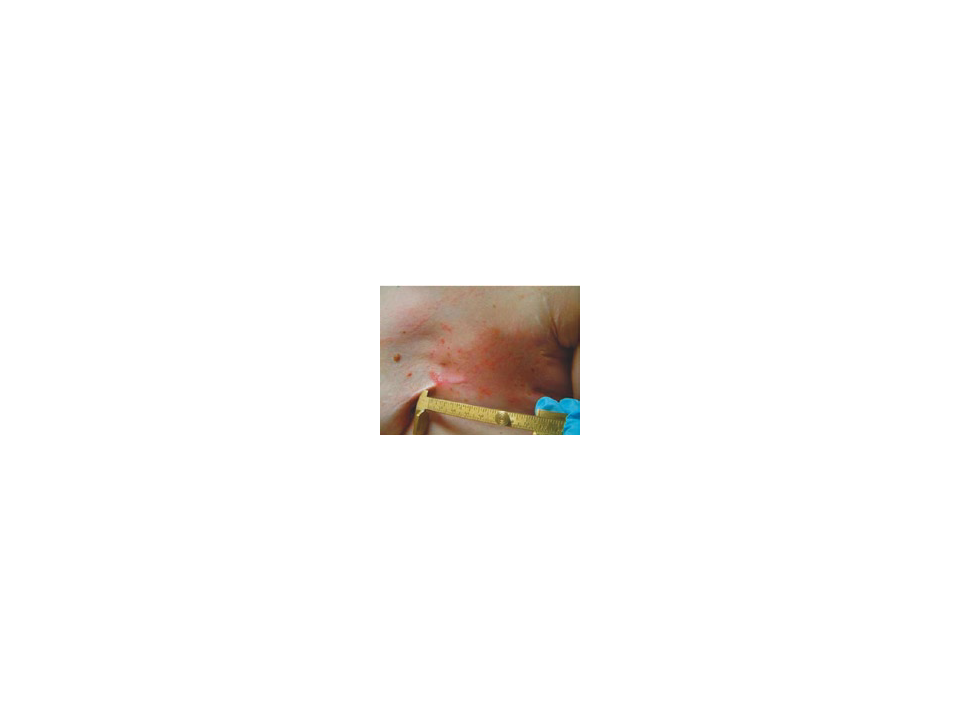

Elektrokemoterapi sistemi; melanoma ve diğer deri tümörleri (gövdeye yerleşik metastaz), basal hücre karsinoma, skomoz hücre karsinoma, kaposi sarcoma, göğüs kanseri kaynaklı lokal rekuranslar ve kutanöz metastazlar, baş-boyun kanserlerinin tedavisinde etkin olarak kullanılmaktadır.

Göğüs kanseri kaynaklı lokal rekuranslar ve kutanöz metastazlarda radyasyon terapisi ile daha önceden tedavi edilmiş alanlarda da etkindir.

Göğüs kanseri kaynaklı lokal rekuranslar ve kutanöz metastazlarda ağrılı, ülserli veya kanamalı lezyonları hafifletir; yaşam kalitesini ve kozmetik sonuçları artırır.